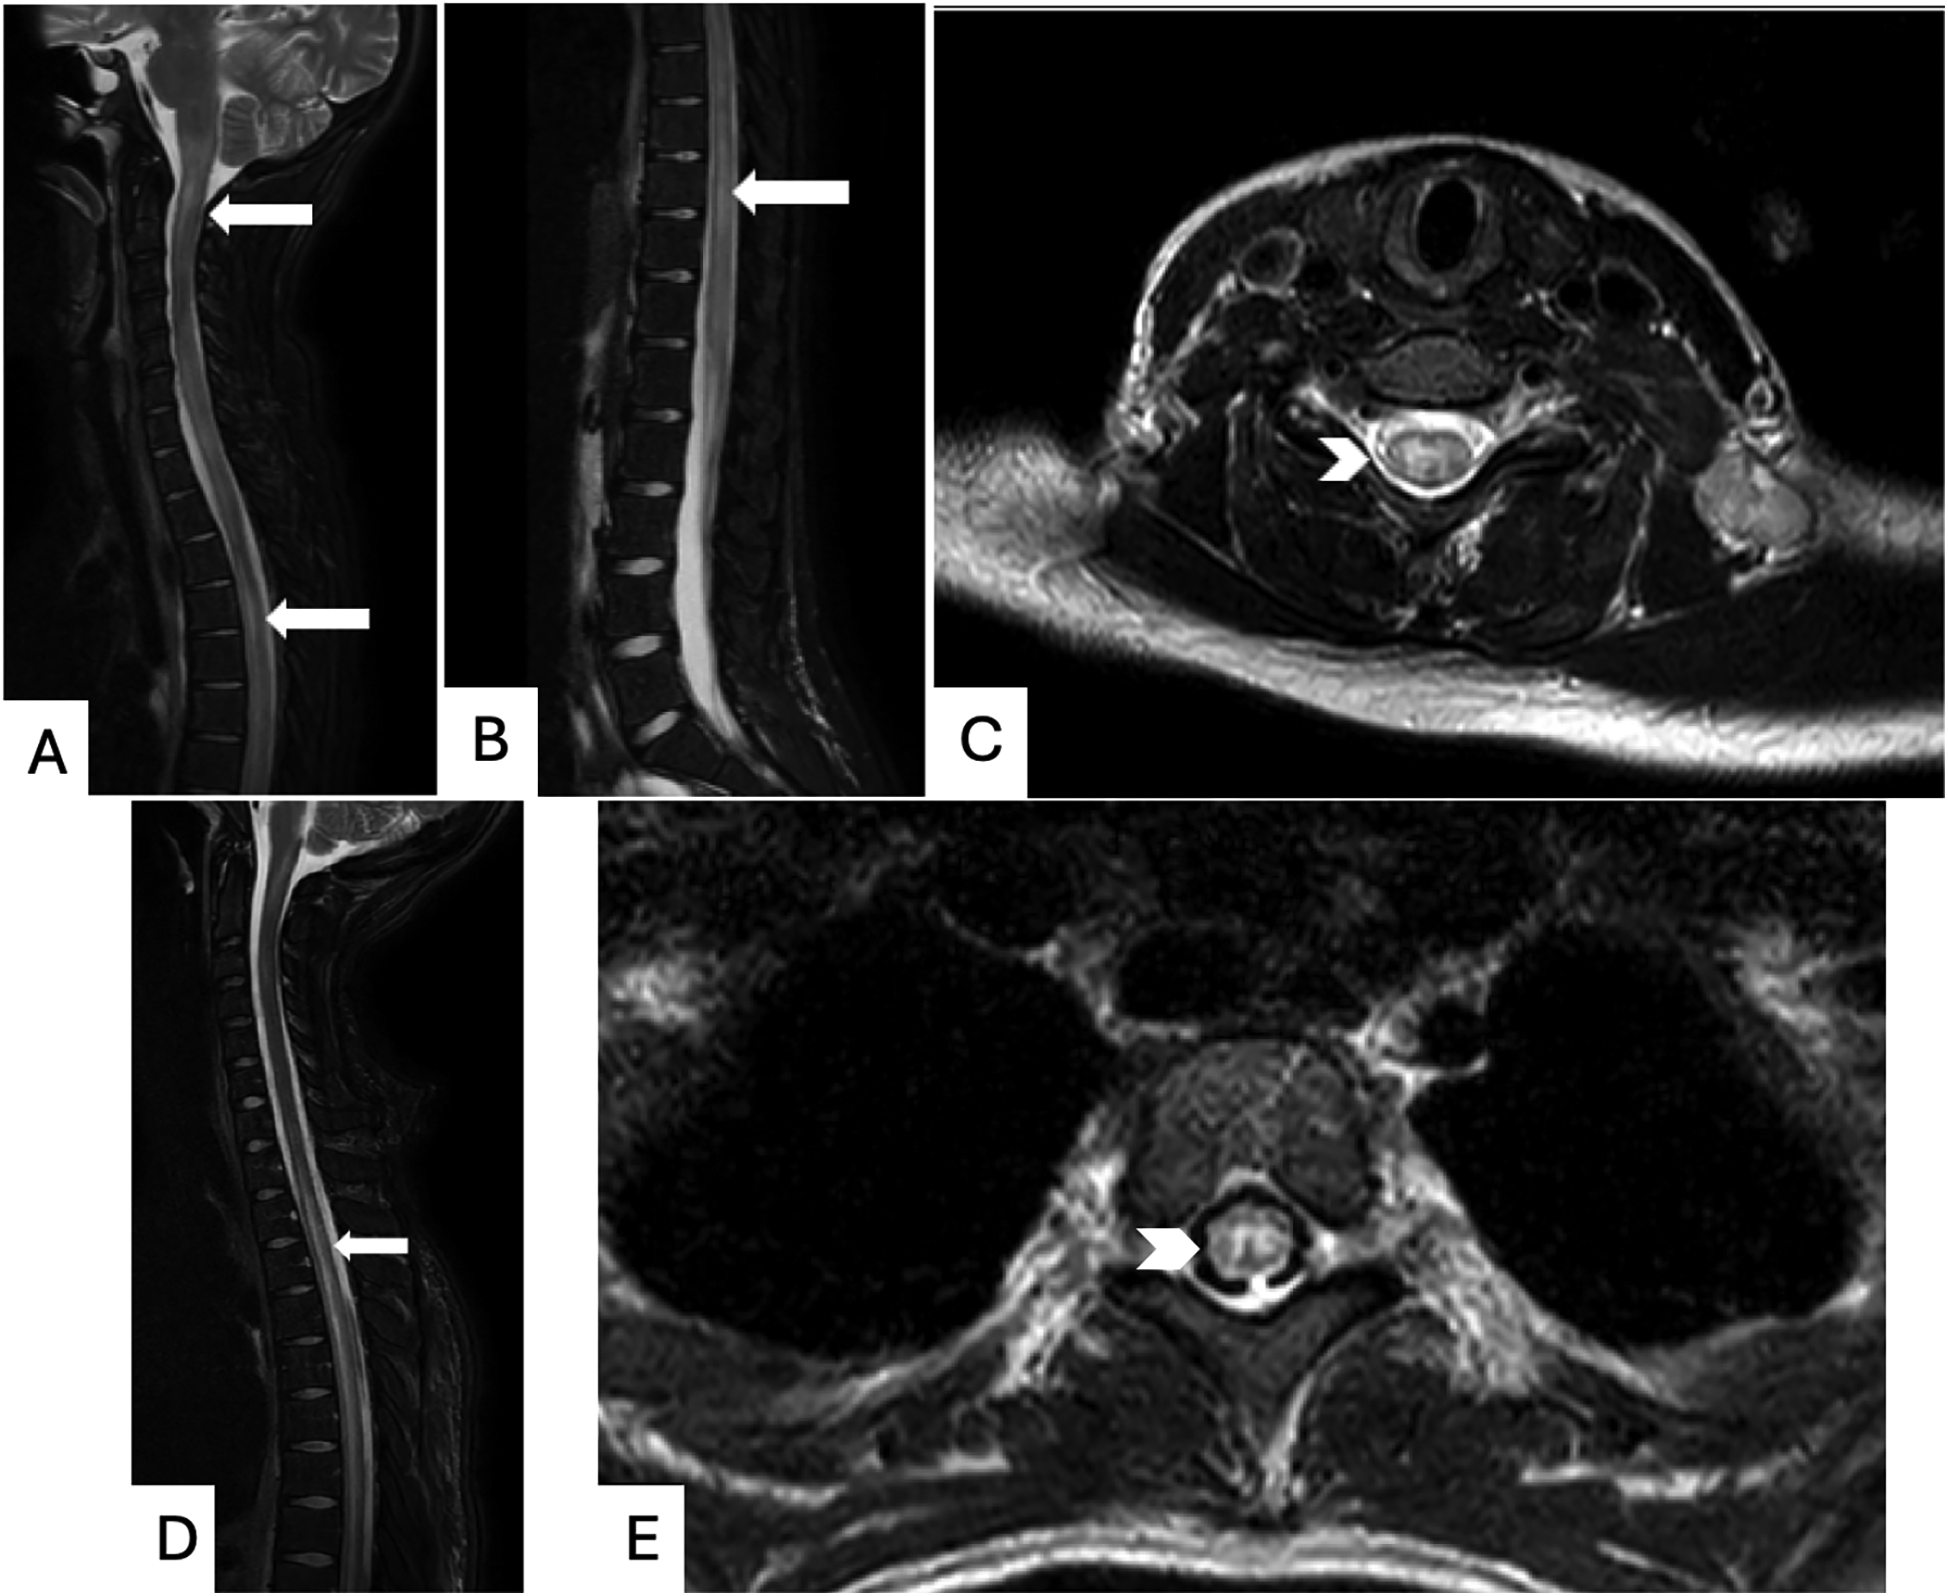

Figure 3

Magnetic resonance imaging (MRI) of the spine: patient 1: T2-weighted MRI images without contrast demonstrating longitudinally extensive T2 hyperintensities in the cervicomedullary junction through cervical and thoracic (A) and lumbar (B) spinal segments (long white arrows), as well as hyperintense signal on axial MRI cervical spine (C) affecting both gray and white matter (thick white arrowhead). Patient 2: T2-weighted Fluid-attenuated inversion recovery (FLAIR) sequence MRI images with Gadolinium contrast demonstrating extensive T2 hyperintensities in the thoracic spinal cord both on sagittal (D) and axial (E) views, demonstrated with long white arrows and thick white arrowhead, respectively.

The care team obtained MRI of the brain and spinal cord, which showed a non-enhancing T2 hyperintensity in the upper cervical spinal cord extending into the cervicomedullary junction as well as a long segment of T2 hyperintensities extending nearly the entire length of her spinal cord, greatest within the central gray matter (Figures 3A–C). Lumbar puncture was performed, and cerebrospinal fluid (CSF) analysis revealed low glucose, elevated protein, and pleocytosis (Table 1). Initial treatment with intravenous immunoglobulin (IVIG) for three days for presumed acute flaccid myelitis resulted in improvement in urinary retention and extremity weakness.

Neurologic consultation recommended MRI of the brain and entire spine with and without contrast, which demonstrated scattered T2 signal abnormalities throughout the spinal cord extending from T1 to the conus medullaris (Figure 3 D and E). She received five days of plasmapheresis and five days of 1,000 mg methylprednisolone IV with subtle improvement in her symptoms. Given elevated inflammatory markers concerning for possible autoimmune process, rheumatologic evaluation was initiated and significant for positive ANA, dsDNA, anti-Sjögren's Syndrome Related Antigen A, anti-ribonucleoprotein (RNP), and anti-Smith autoantibodies in addition to hypocomplementemia. Laboratory findings in conjunction with neuroimaging findings met SLICC classification criteria for a diagnosis of SLE complicated by lupus myelitis (see Table 1). Diagnosis was formally made on day 11 of her admission. She received cyclophosphamide and rituximab after diagnosis of SLE was established and continued with weekly doses of 1,000 mg methylprednisolone IV.